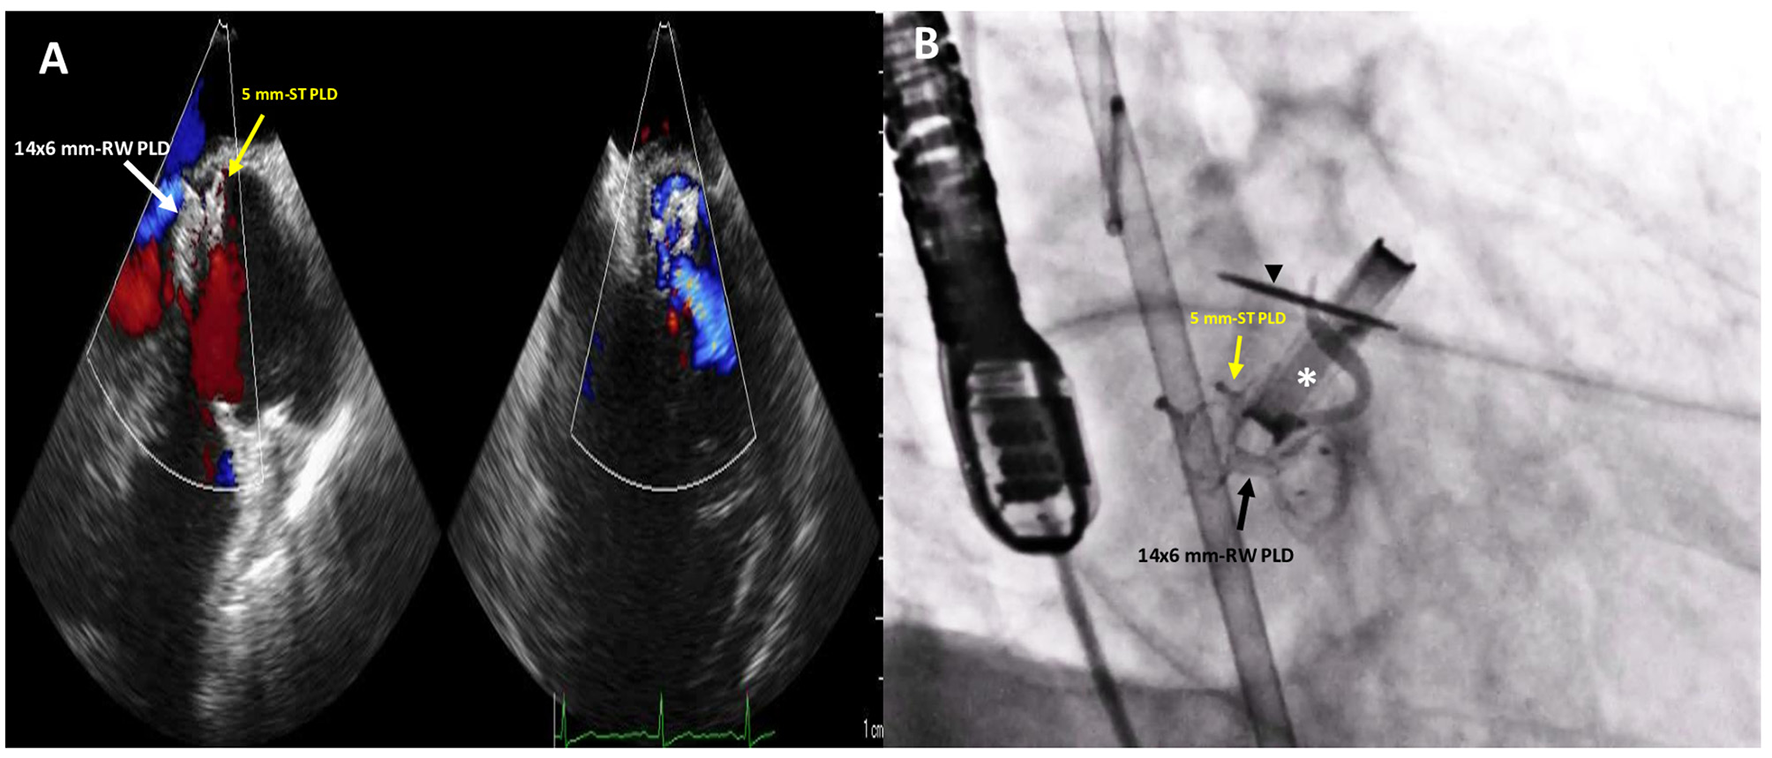

Figure 4

Post-procedure 2D TTE color Doppler (A) and fluoro-angiographic (B) images showing the correct and stable position of the two PLDs not impinging on the tilting disc (black arrowhead) of the mechanical aortic valve (white asterisk) with only trivial residual regurgitant jet.